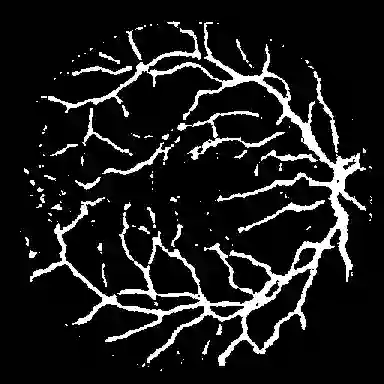

Foundation segmentation models such as the Segment Anything Model (SAM) exhibit strong zero-shot generalization through large-scale pretraining, but adapting them to domain-specific semantic segmentation remains challenging, particularly for thin structures (e.g., retinal vessels) and noisy modalities (e.g., SAR imagery). Full fine-tuning is computationally expensive and risks catastrophic forgetting. We propose \textbf{TopoLoRA-SAM}, a topology-aware and parameter-efficient adaptation framework for binary semantic segmentation. TopoLoRA-SAM injects Low-Rank Adaptation (LoRA) into the frozen ViT encoder, augmented with a lightweight spatial convolutional adapter and optional topology-aware supervision via differentiable clDice. We evaluate our approach on five benchmarks spanning retinal vessel segmentation (DRIVE, STARE, CHASE\_DB1), polyp segmentation (Kvasir-SEG), and SAR sea/land segmentation (SL-SSDD), comparing against U-Net, DeepLabV3+, SegFormer, and Mask2Former. TopoLoRA-SAM achieves the best retina-average Dice and the best overall average Dice across datasets, while training only \textbf{5.2\%} of model parameters ($\sim$4.9M). On the challenging CHASE\_DB1 dataset, our method substantially improves segmentation accuracy and robustness, demonstrating that topology-aware parameter-efficient adaptation can match or exceed fully fine-tuned specialist models. Code is available at : https://github.com/salimkhazem/Seglab.git